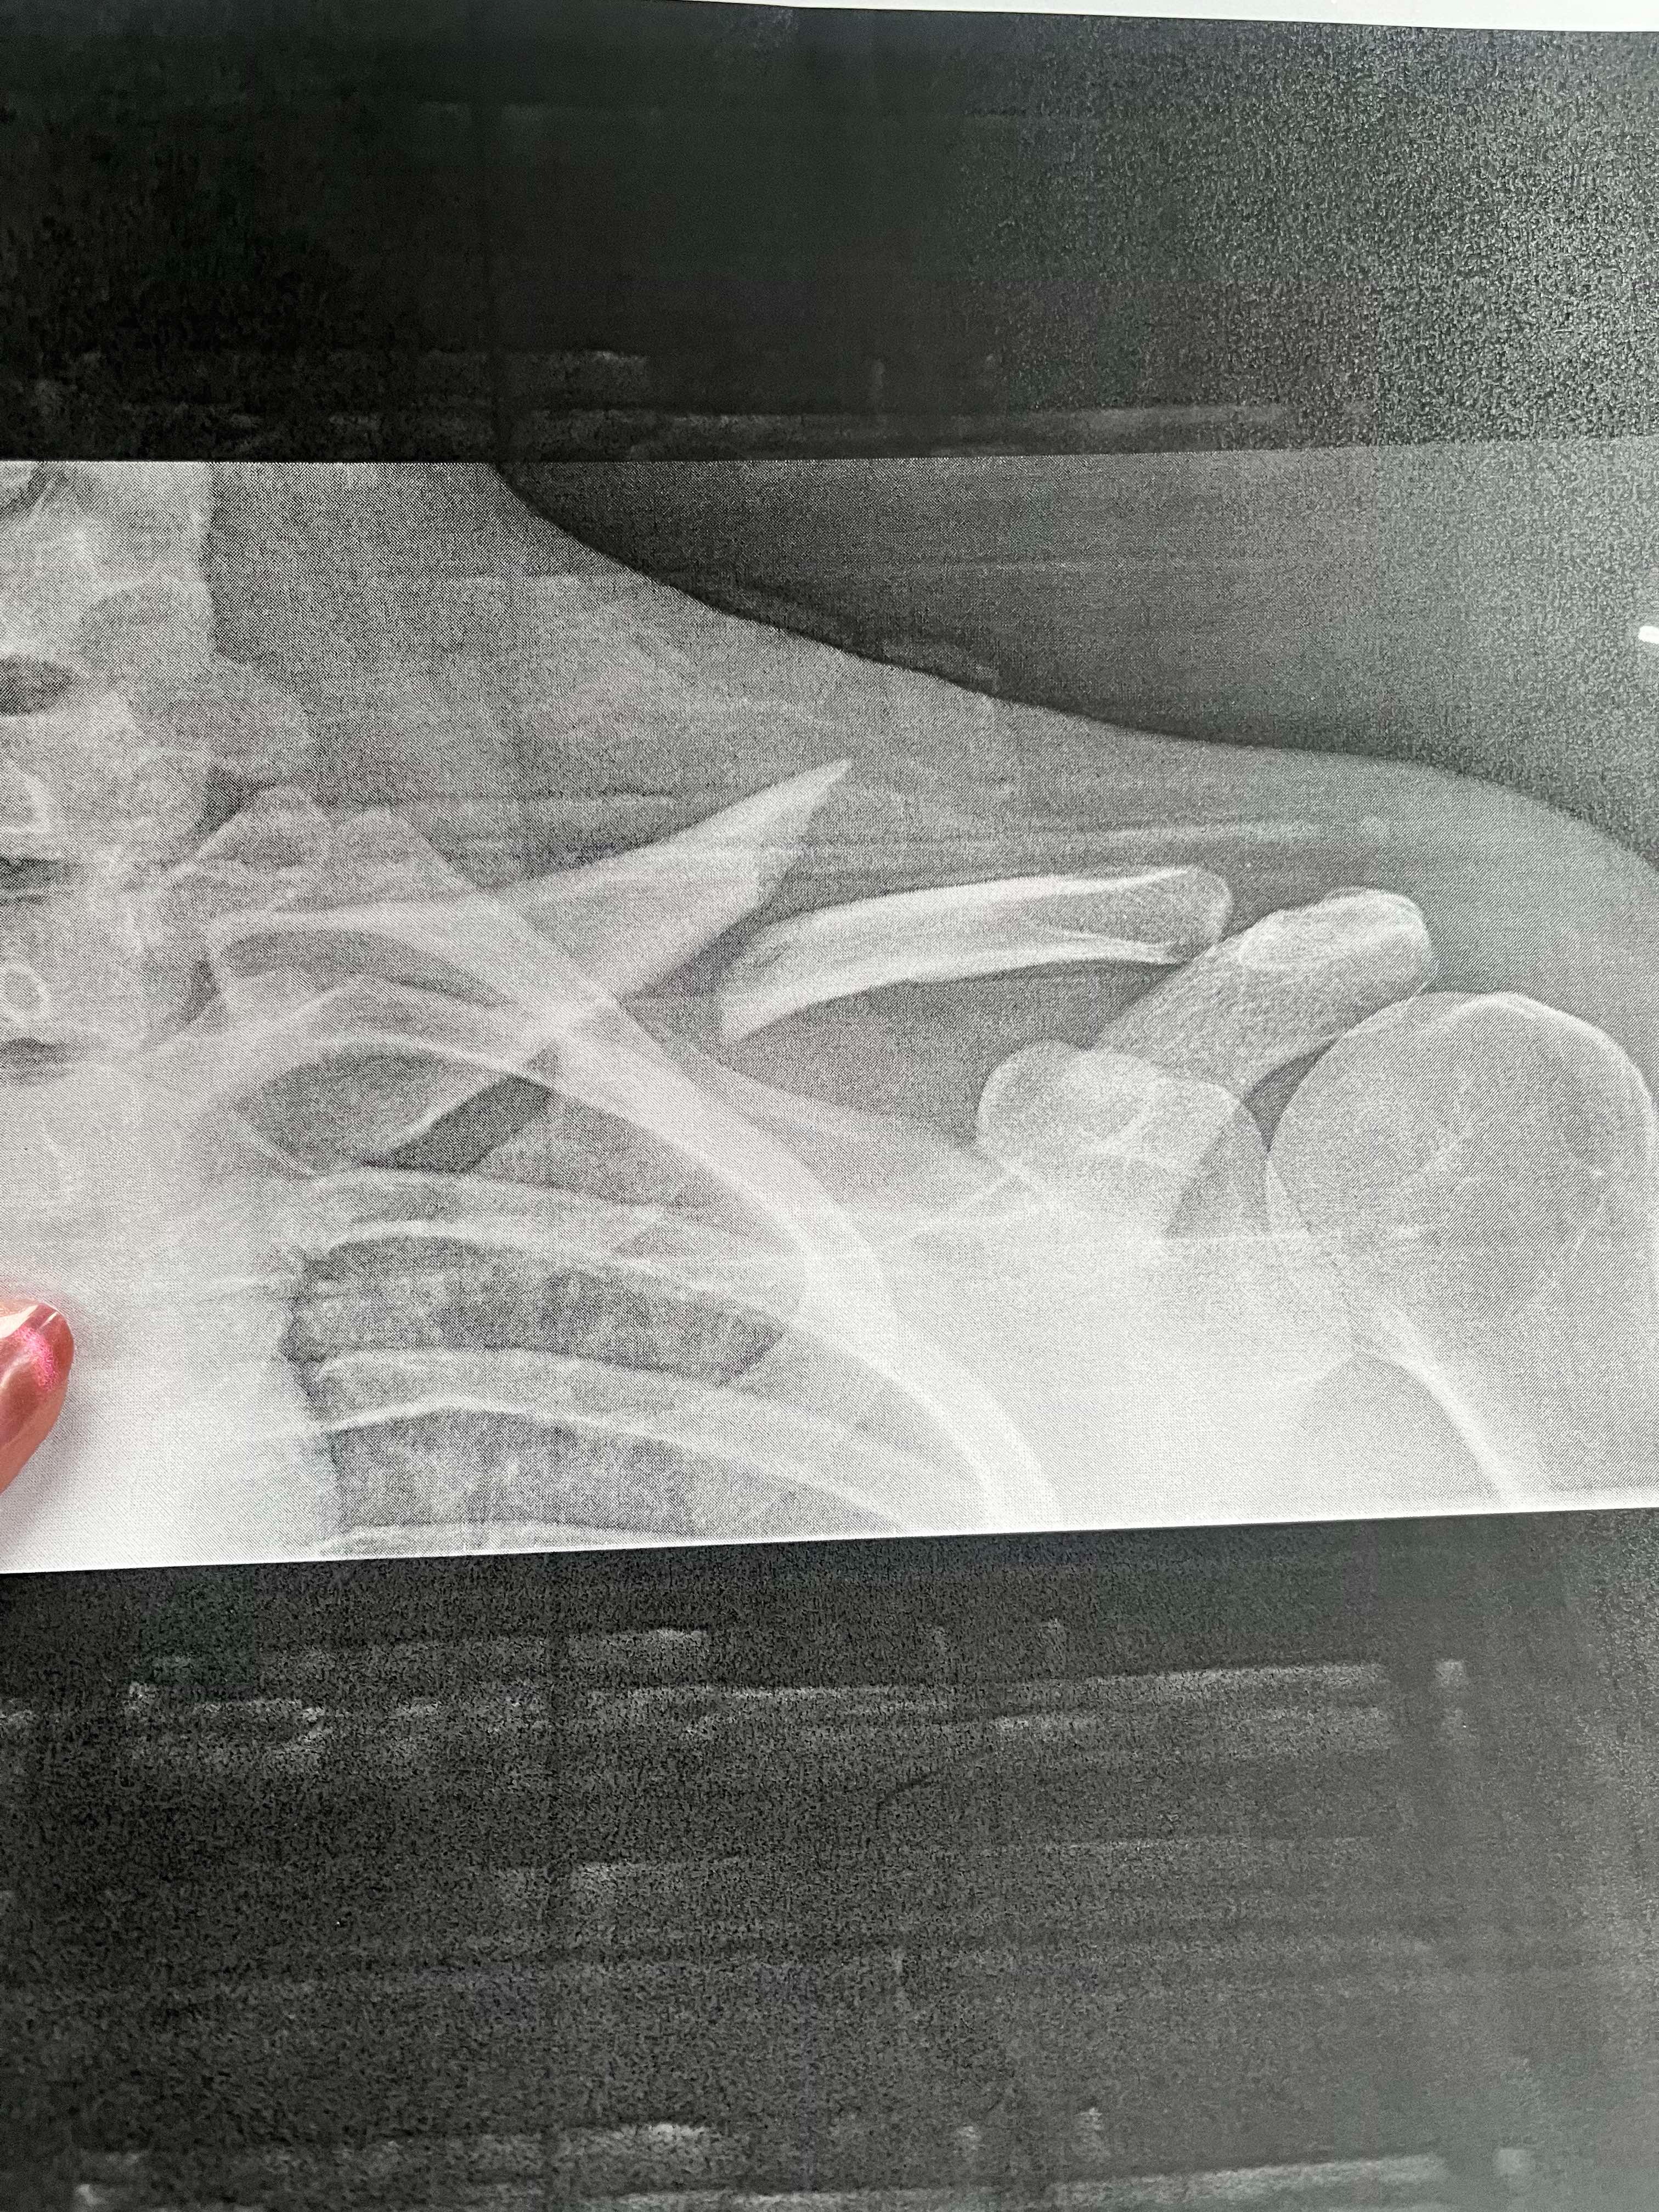

Hello everyone, my name is Jackie Evans. About 2 weeks ago, I had a very good friend and work colleague that I consider family get into a very bad car accident. Most people may know Skylar Rock and how great of a person she is. She would do anything to help anyone, so I'm reaching out for help for her. I won't go into too many details, but the wreck has left her with a broken foot and collarbone, putting her out of work for 6 weeks minimum. She had an orthopedic visit today, where she found out that her collarbone had separated and shifted more, meaning that in 4 weeks' time she may have to have surgery if it doesn't start healing the way the doctors would like. This would put her out for an additional 8 weeks roughly, depending on what her doctor says at that point. She is a server, which means she solely depends on tips and has no other income, and she is also currently still a student.